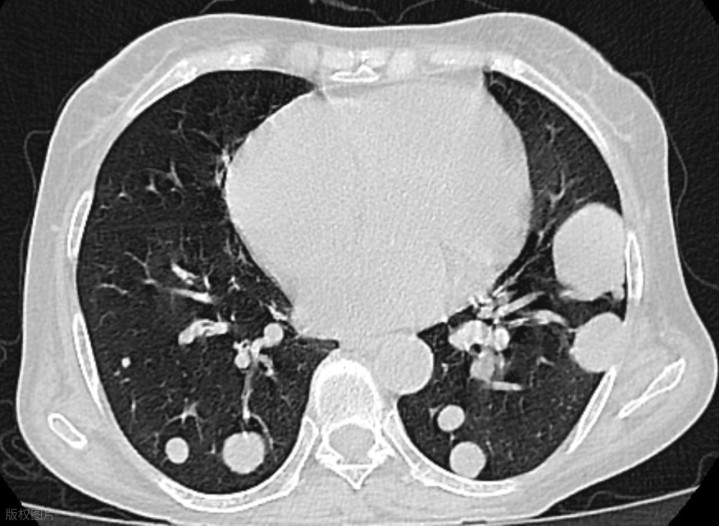

之前门诊的一位患者,55岁男性,因体检发现左肺有一个约8mm的结节而就诊。

患者自述有持续的咳嗽症状,咳痰较多,痰质黏稠,晨起时咳嗽较为严重,且伴有轻微的胸闷感。

两个月后,患者咳嗽减轻,咳出的痰量和黏稠度都明显下降,胸闷感明显减轻,体力也逐渐恢复,食欲明显改善。复查肺部时,发现原先的结节已经明显缩小。